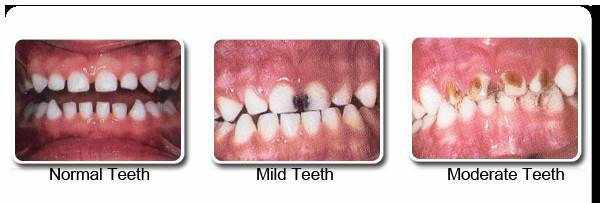

氟对防龋的效果是毋庸置疑的,因此,使用含氟牙膏也是防龋的有效手段之一。但是,对于孩子是否能使用含氟牙膏,一直备受争议。

因为凡事有利必有弊,若牙齿在发育期间暴露在过高浓度氟化物中,牙齿发育会受到影响,引起氟斑牙(如下图)。

那我们的宝贝到底应不应该使用含氟牙膏呢?为了最大化地利用氟的防龋能力,同时尽量减小氟斑牙产生几率,美国牙医协会给出如下建议: